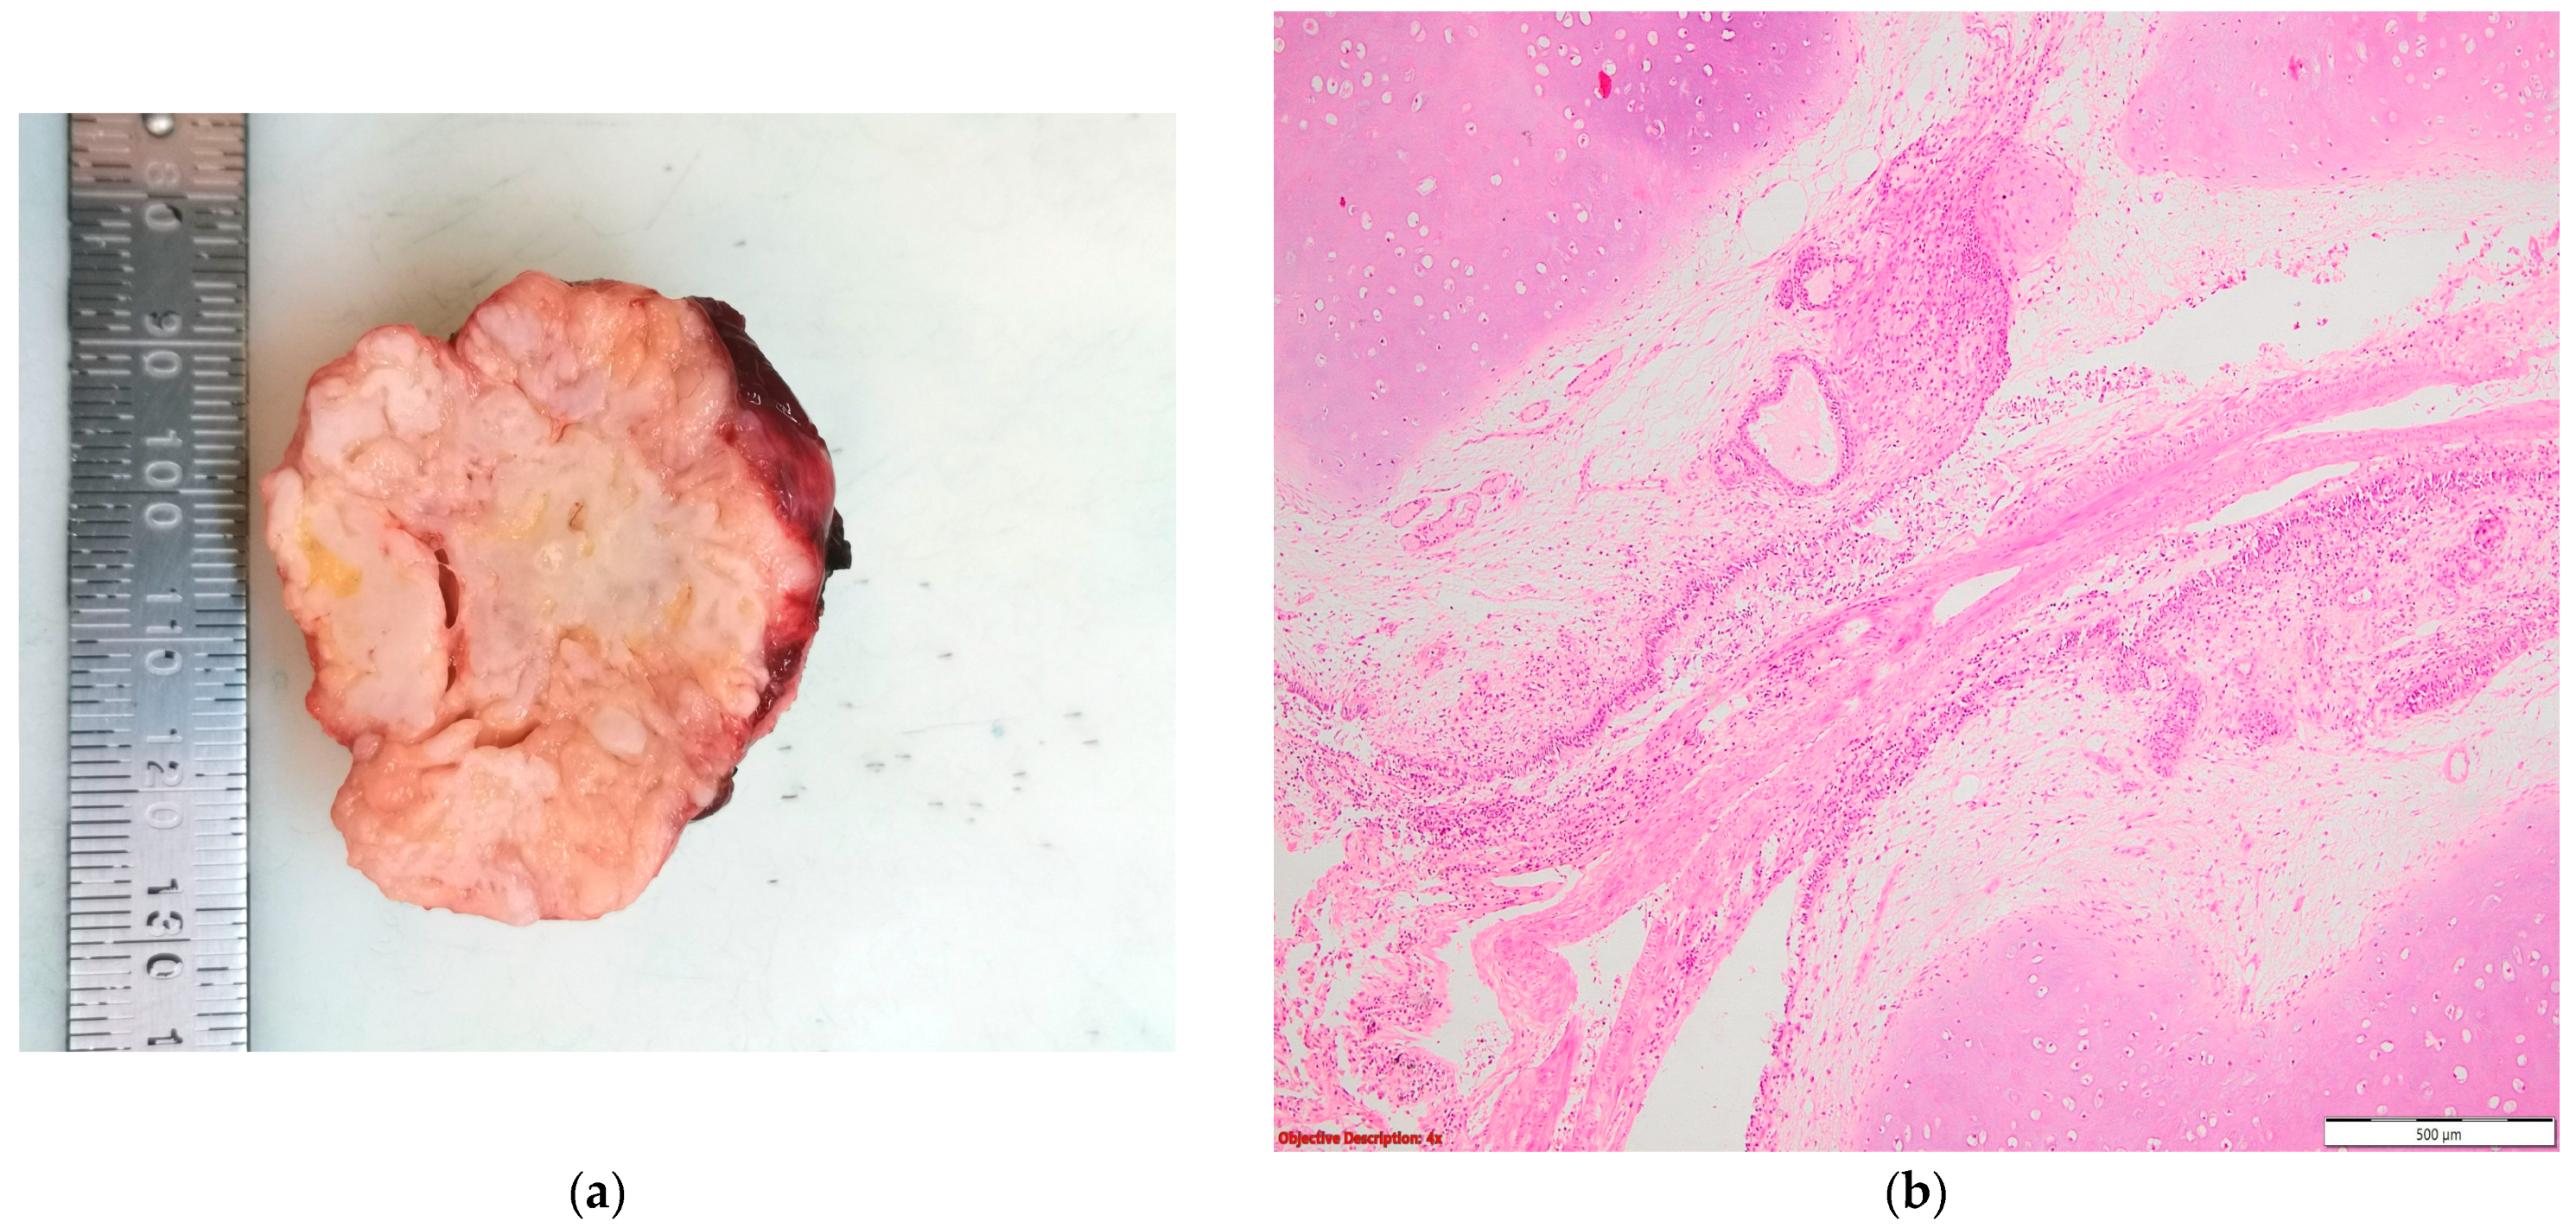

Figure 6. Lung adenocarcinoma: (a) gross examination (white tumor with polycyclic contour and anthracotic deposits); and (b) microscopic examination (tumoral glands that replace the normal lung parenchyma); HE, 40×.

Two of the specimens with fibronodular lesions were associated with multiple NSCLC tumors of different histopathological subtypes: one case presented with adenocarcinoma (one tumor—Figure 6) and a squamous cell tumor (one tumor—Figure 7) and another case presented with adenocarcinoma (one tumor) and large-cell neuroendocrine tumors (two tumors—Figure 8).